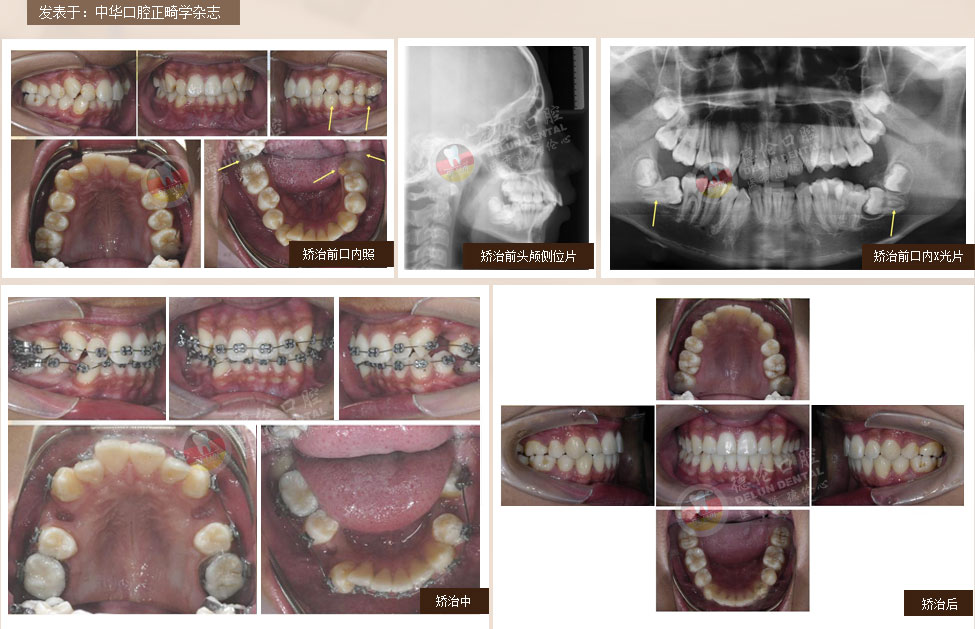

症状:下颌右侧第二、第三磨牙水平阻生,下颌左侧第三磨牙水平阻生

矫治方法:下颌拔除两颗第三磨牙(智慧齿)

症状:牙列不齐、下颌第二、第三磨牙水平阻生,左侧磨牙锁牙合

矫治方法:拔除上颌及右下第一双尖牙,左下第二双尖牙以及2个下第三磨牙